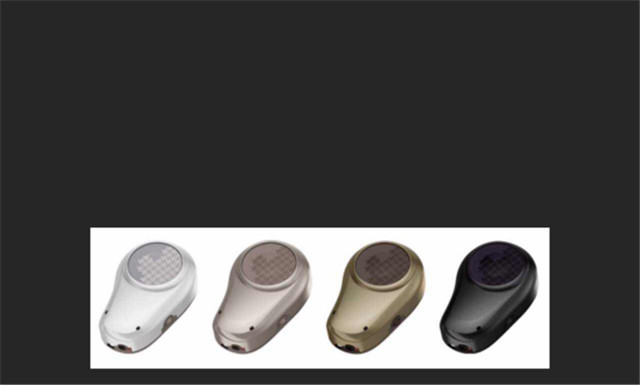

附機(jī)器圖片: